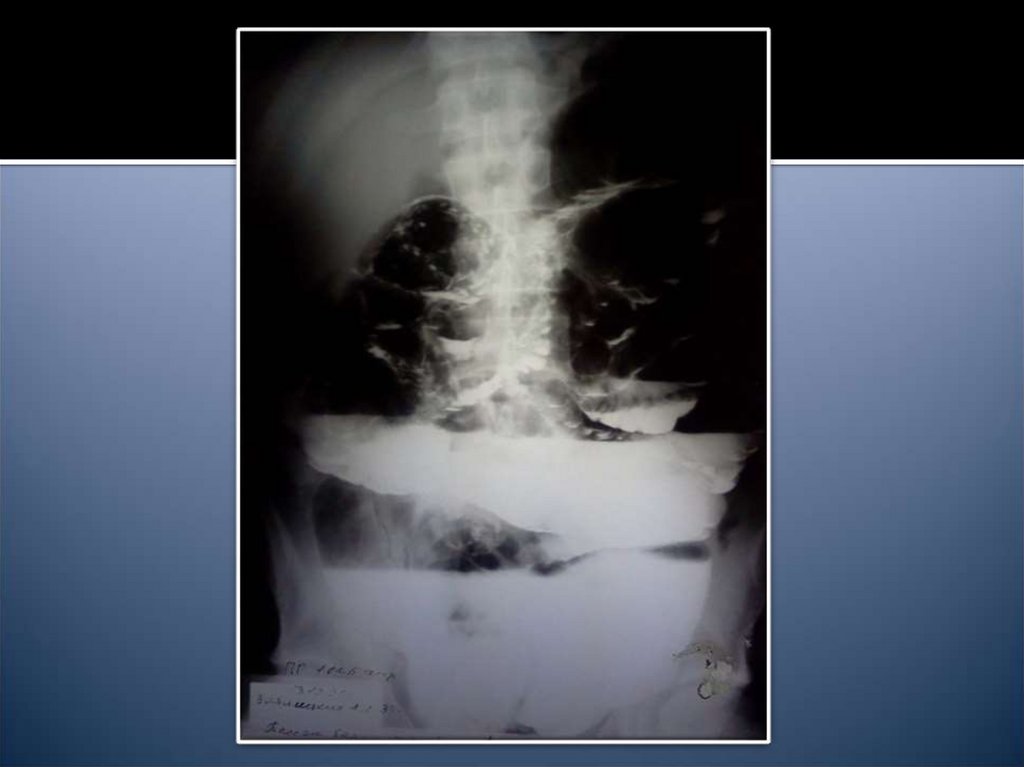

14. Рентгенологические признаки

Чаши Клойбера

Симптом Кивуля (аркады)

Проба Шварца

Пневматоз петель кишечника